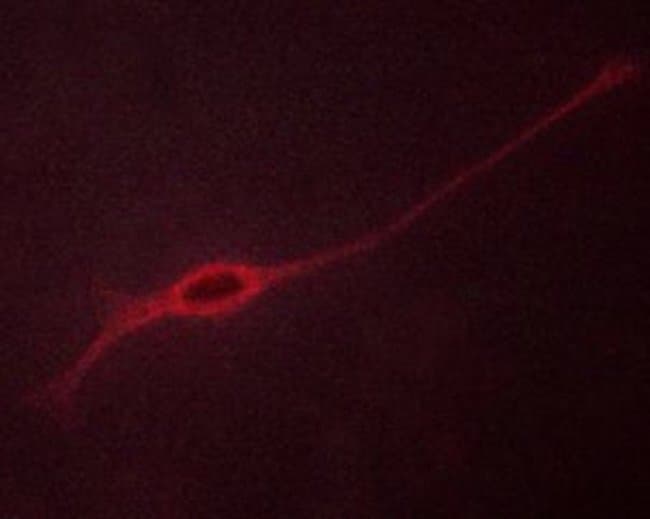

| Immunohistochemistry (Paraffin), Western Blot, Immunocytochemistry | |

Invitrogen™ Phospho-TRKB (Tyr706) Polyclonal Antibody

Antibody detects endogenous levels of Trk B only when phosphorylated at Tyrosine 706.